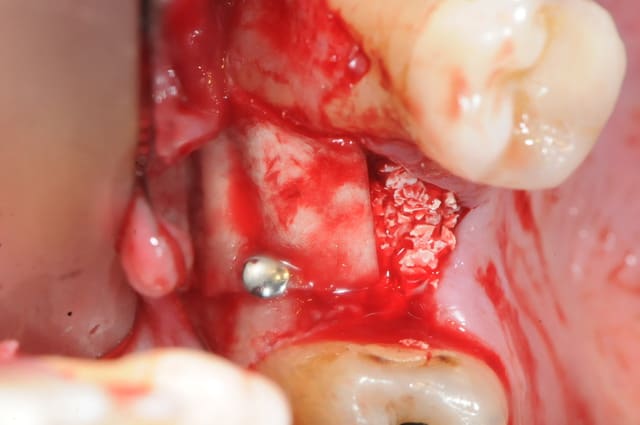

1&2 : réalisation à l'aide d'une tréphine de la fenêtre vestibulaire pour aller plus vite et surtout pour pouvoir réutiliser plus tard ce petit bloc osseux.

( vous verrez plus atrd à quoi ça sert)

3: fenêtre et CBS bien visibles

j'aurai aimé faire mon abord latéral plus haut, mais je vous rappel que l'on est au niveau de la 7 et que c'est difficile d'écarter les tissus.

(Rachel qui m'a gentiment assisté à beaucoup souffert de tétanisation musculo-palmaire multiple)

vous noterez tout de suite la différence de teinte entre un sinus sain et avec ici, un sinus hyper inflammatoire et infecté (une vraie cocotte-minute)